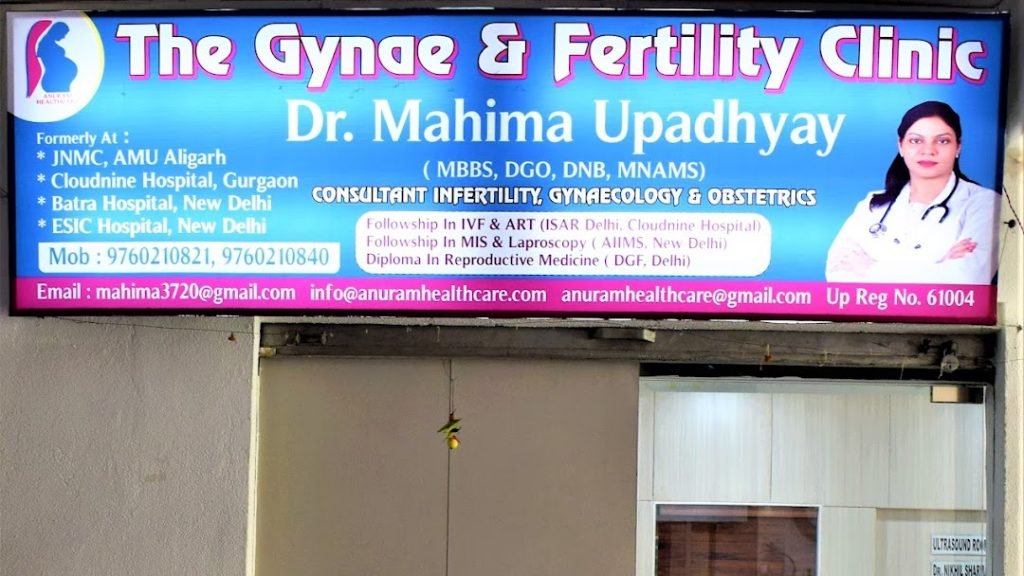

Dr. Mahima Upadhyay ( The Gynae and Fertility Clinic)-Best gynecologist in Agra | Best IVF center in Agra

First Floor , Shanti Madhuban Plaza Delhi Gate Road Agra, Uttar Pradesh 282002 India

First Floor , Shanti Madhuban Plaza Delhi Gate Road Agra, Uttar Pradesh 282002 India